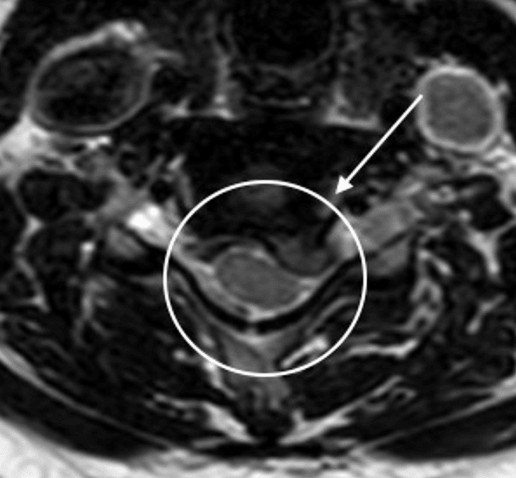

경추에는 C1부터 C7까지 표시되어 있는 7개의 척추뼈가 서로 쌓여 있습니다. 추간판은 인접한 척추체 사이에 위치합니다. 예를 들어, C5-C6 디스크는 C5와 C6 척추 사이에 위치합니다. C5-C6 디스크가 탈출되면 C6 신경근을 압박할 수 있습니다. 경추 추간판 탈출증으로 인한 징후와 증상은 어느 신경근이 압박되는지에 따라 달라질 수 있습니다.

C5-C6(C6 신경근): 손의 엄지손가락 부분에 통증, 따끔거림 및/또는 무감각이 느껴질 수 있습니다. 이두근(팔뚝 앞쪽에 있는 근육)과 팔뚝에 있는 손목 신근 근육에서도 쇠약이 나타날 수 있습니다. C5-C6 디스크는 가장 흔한 탈출증 중 하나입니다. 1

C6-C7(C7 신경근): 통증, 따끔거림 및/또는 무감각이 손과 중지로 퍼질 수 있습니다. 삼두근(팔 위쪽 뒤쪽의 근육), 손가락 신근 및 기타 근육에서도 쇠약이 느껴질 수 있습니다. C6-C7 디스크는 일반적으로 경추에서 탈출 가능성이 가장 높은 것으로 간주됩니다. 1